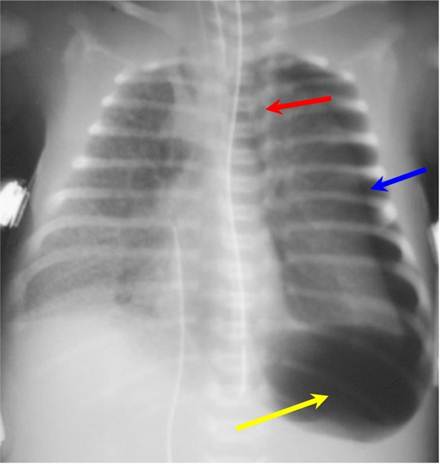

图3 左侧张力性气胸(蓝箭头)压迫心脏和纵隔结构右移(红箭头);此病例,左侧有一个深沟征(黄箭头)。有潜在的透明膜病。